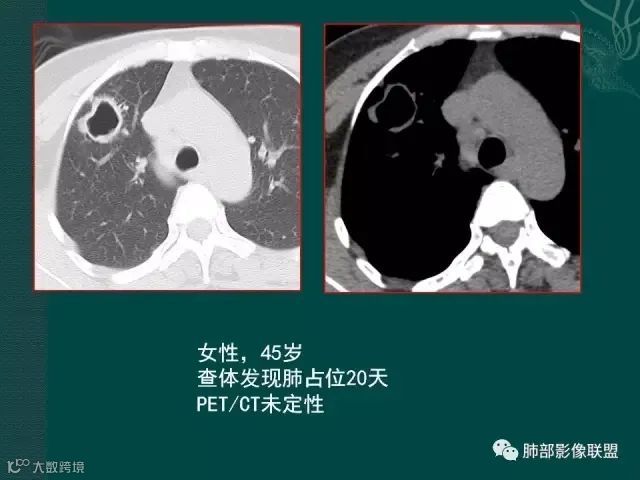

定要记住,在免疫力低下,或白细胞降低的病人,如果在化疗过程中出现痰中带血,最大可能不是肿瘤进展,也不是侵犯血管,而是侵袭性的肺曲霉菌感染。

该病例进展较快,悬球征-霉菌感染的特异征象。

病史似乎是炎性;空洞型病变,靠近纵隔的时候,一定要看对纵隔是否有侵蚀,这是相当重要的。